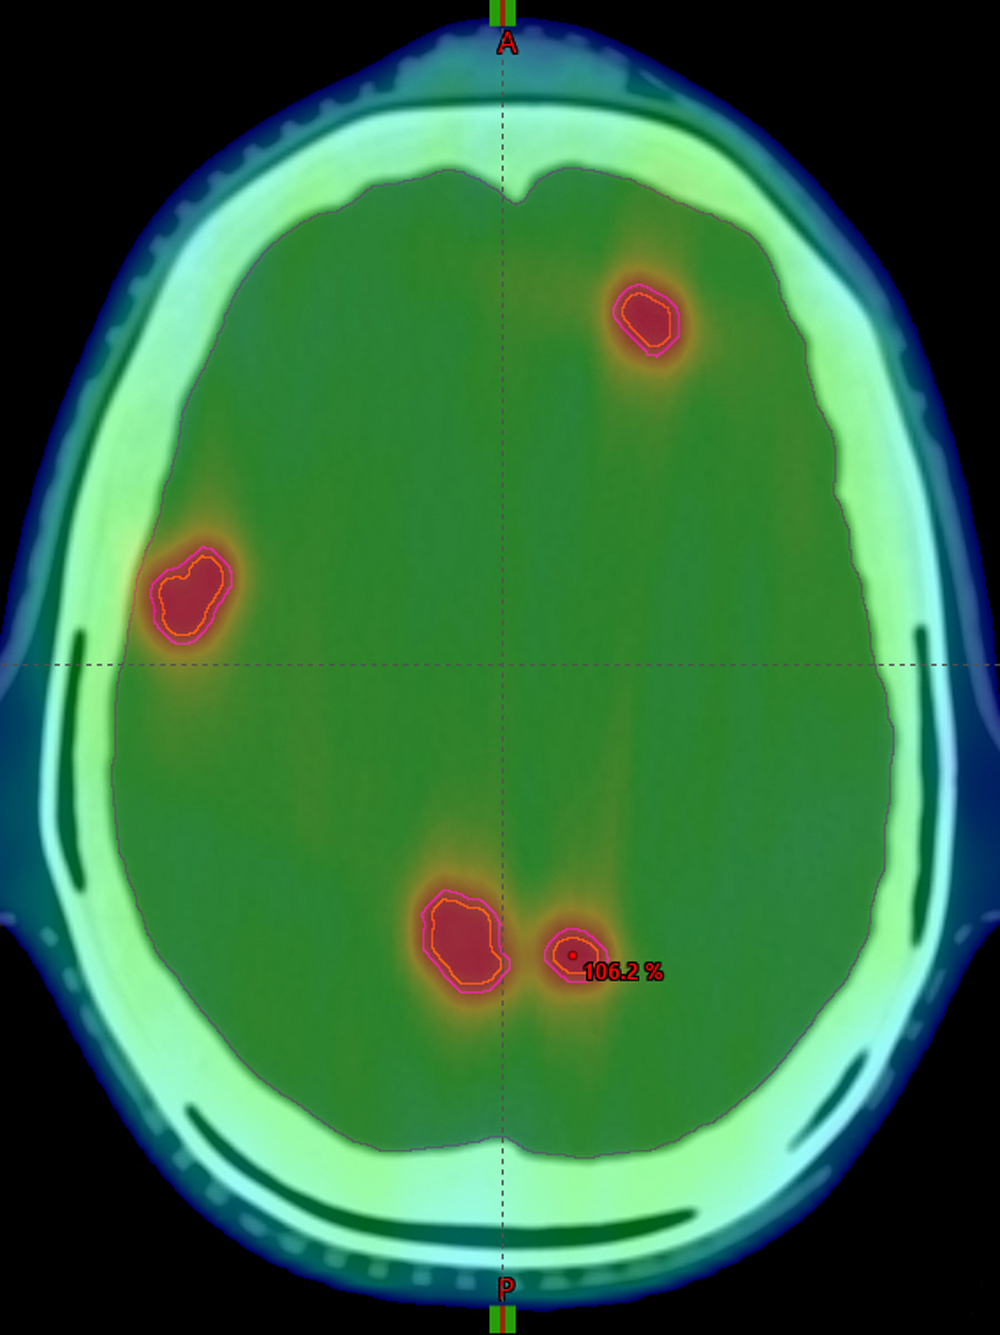

Entwicklungen der letzten Jahre ermöglichen heutzutage die hochpräzise Bestrahlung sehr kleiner Tumoren. Besonders profitieren davon Patient*innen mit Hirnmetastasen. Mittlerweile können sogar mehrere Metastasen gleichzeitig in einer Bestrahlungssitzung behandelt werden. Doch je kleiner die Tumoren sind und je mehr es sind, umso schwieriger ist die Planung der Bestrahlung. In einem neuen Projekt werden Wissenschaftler*innen unter Leitung der Klinik für Strahlenheilkunde des Universitätsklinikums Freiburg zum ersten Mal präzise ermitteln, wie sich Faktoren Lage, Größe und Zahl der Zielstrukturen auf die Bestrahlungspräzision auswirken. Darauf aufbauend sollen allgemeine Richtlinien für die individuelle Therapieplanung erarbeitet werden. Die Deutsche Krebshilfe fördert das Projekt im Rahmen des Programms „Versorgungsmaßnahmen und -forschung“ mit rund 600.000 Euro.

Die Schwierigkeit bei der Simultanbestrahlung: Neben der Anzahl und Größe der Metastasen führen auch die unterschiedlichen Abstände der Metastasen zueinander und zum virtuellen Bestrahlungszentrum zu technisch bedingten Unsicherheiten. „Mit unserer Forschung wollen wir diese neue Technik der Simultanbestrahlung noch sicherer und präziser machen“, sagt Studienleiter Prof. Dr. Dimos Baltas, Leiter der Abteilung für Medizinische Physik der Klinik für Strahlenheilkunde am Universitätsklinikum Freiburg.